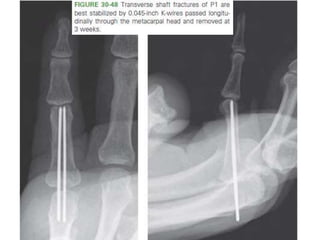

• #81 Transverse shaft fractures of P1 are best stabilized by 0.045-inch K-wires passed longitudinally through the metacarpal head and removed at 3 weeks.

Closed Reduction +Internal Fixation. • Reducible but unstable isolated fractures. • For long oblique and spiral fractures – three K-wires- perpendicular to the fracture • For neck fractures- – retrograde pinning may be necessary • For short oblique and transverse fractures, – longitudinal K-wires .

– longitudinal K-wires .